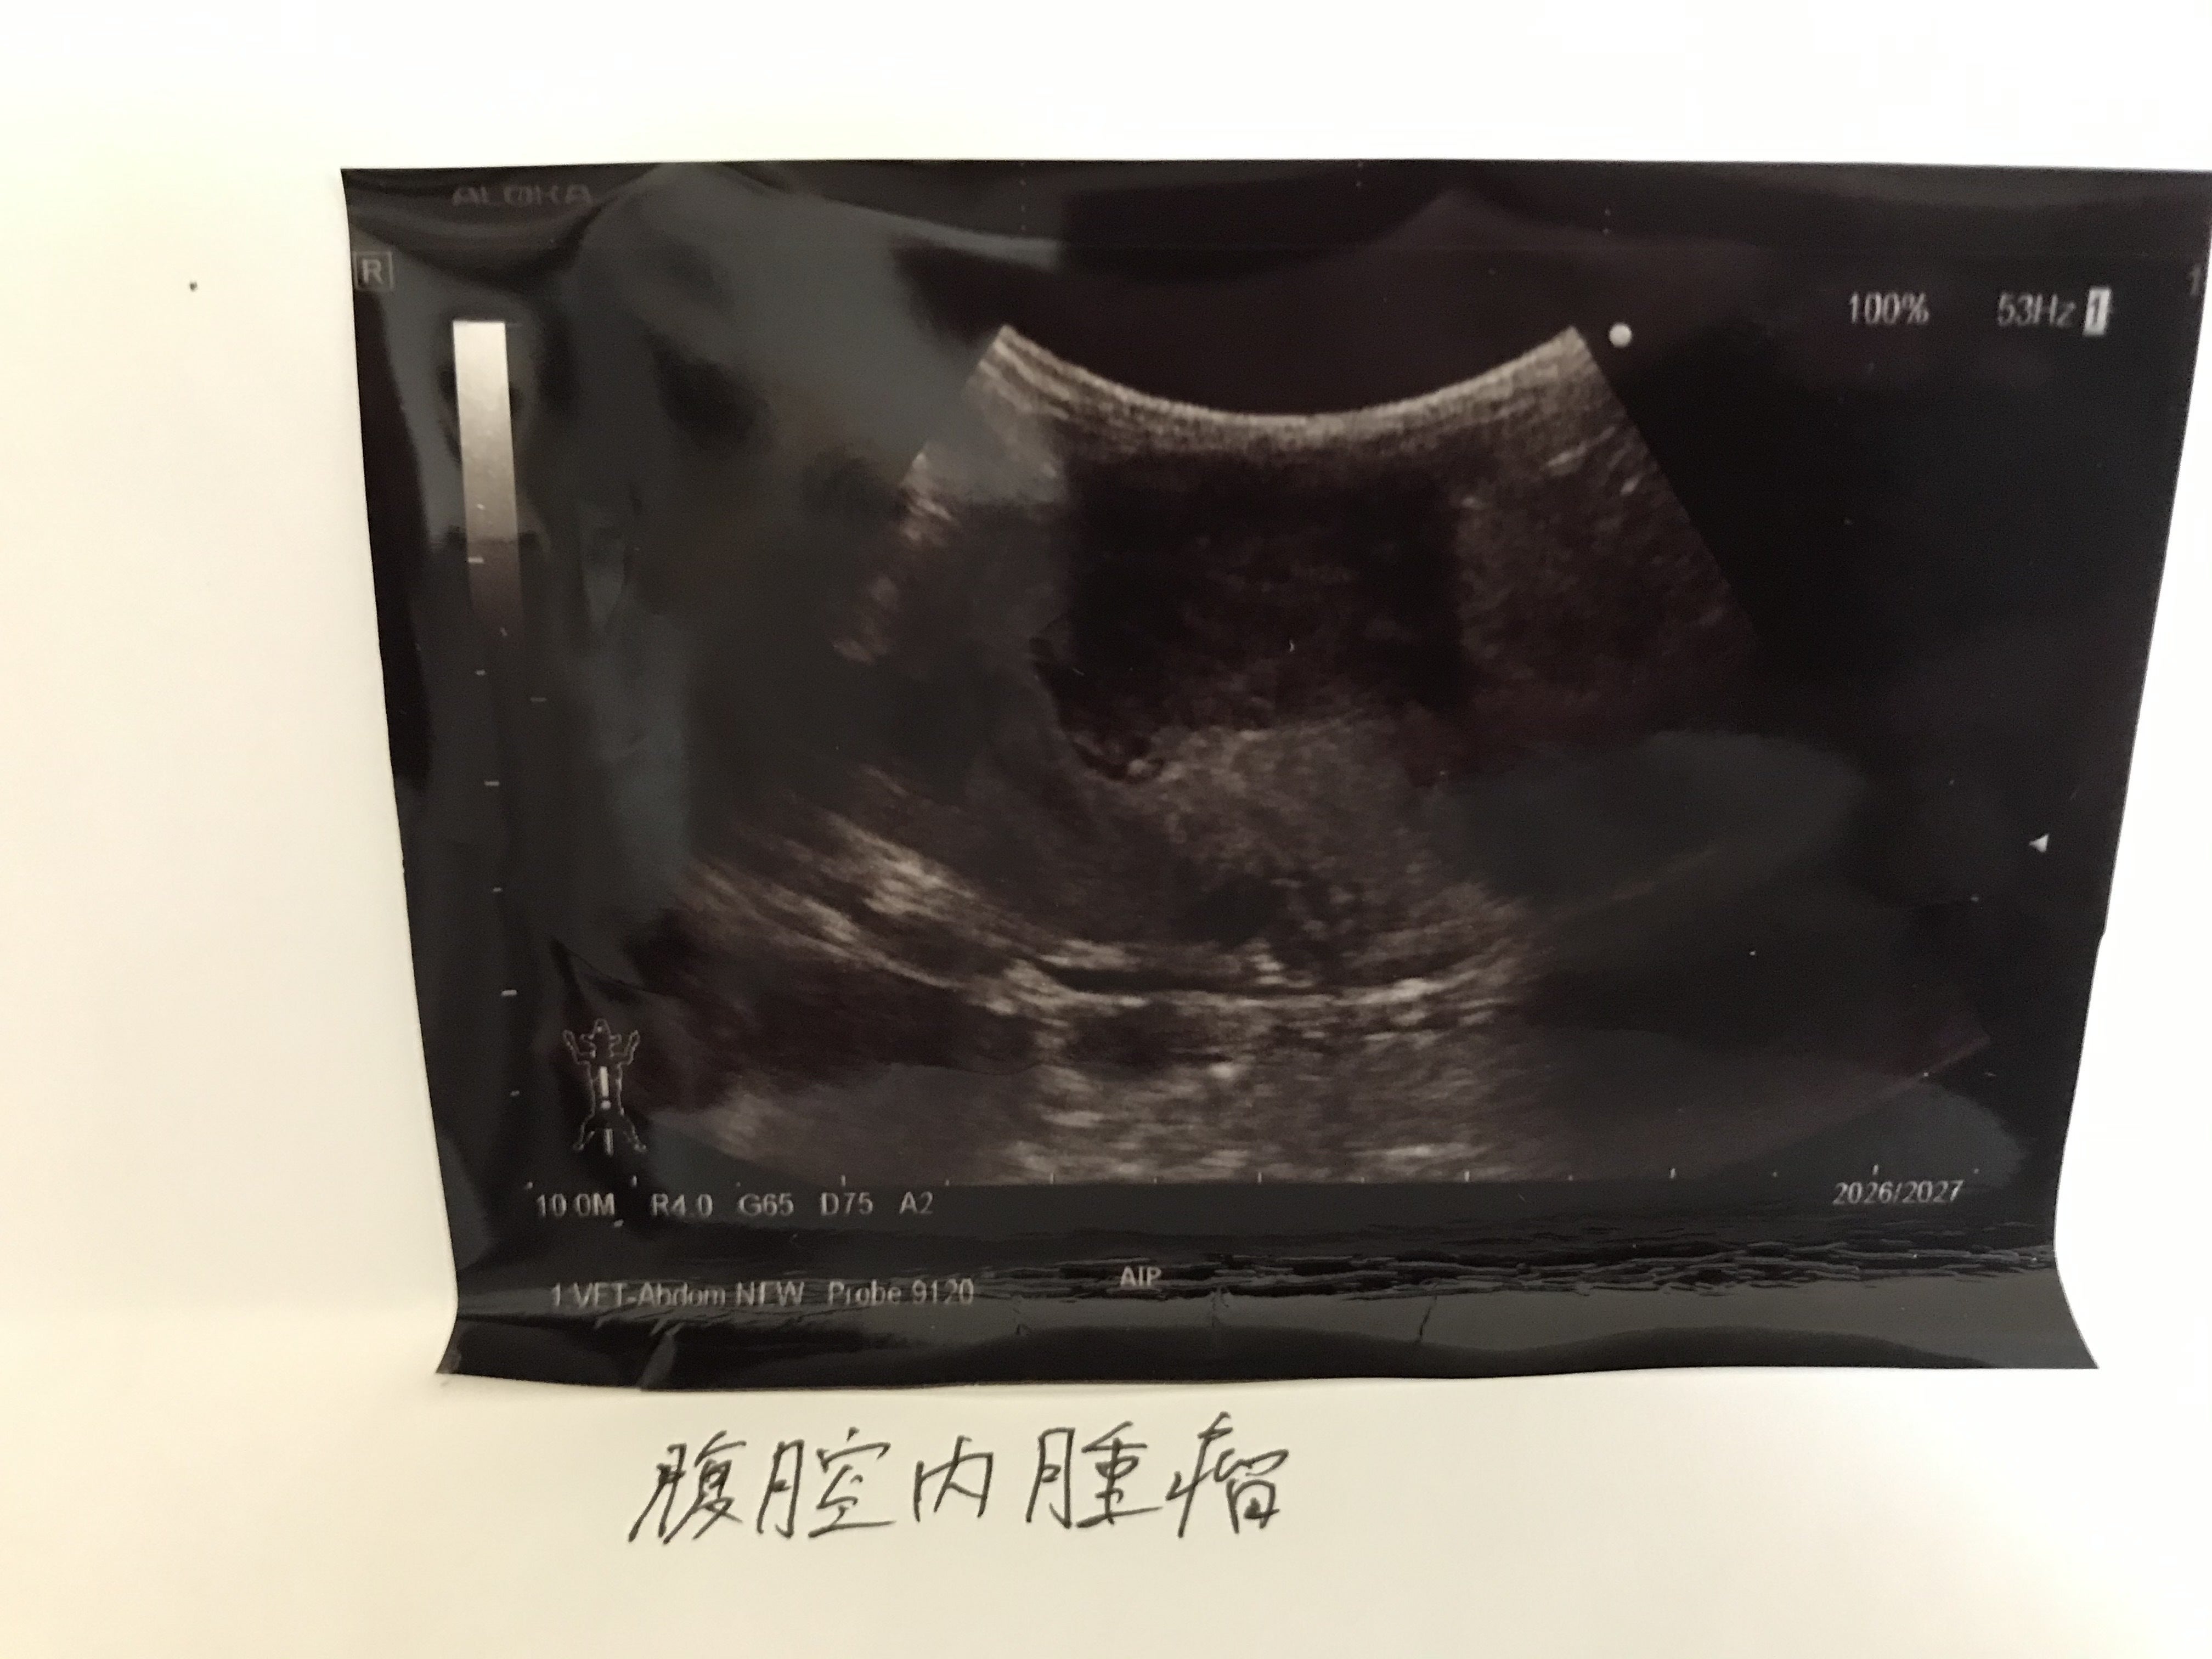

高熱があったこともあり、念のため超音波検査をしたところ、腹水が3つ見つかりました。